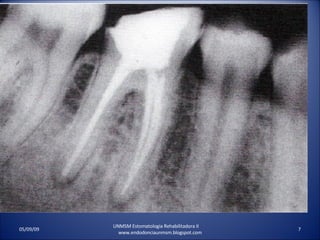

ABSCESO PERIRRADICULAR AGUDODOLOR A AL PRESION. DOLOR AL MORDER. DOLOR A LA PALPACION. DOOR A LA PERCUSION. NO RESPONDE A LA PRUEBA DE VITALIDAD. MOVILIDAD VARIABLE. RX. ENSANCHAMIENTO DEL LIG. PERIODONTAL HASTA RADIOLUCIDEZ PERIRRADICULAR . UNMSM Estomatologia Rehabilitadora II www.endodonciaunmsm.blogspot.com 06/10/09

ABSCESO PERIRRADICULAR CRONICONO RESPONDE A LA PRUEBA DE VITALIDAD PULPAR. RX. RADIOLUCIDEZ PERIRRADICULAR. PIEZA DENTAL INSENSIBLE A LA PRESION. EL PACIENTE LO NOTA DIFERENTE. MUESTRA SUPURACION INTERMITENTE POR UN TRACTO SINUSAL ASOCIADO. UNMSM Estomatologia Rehabilitadora II www.endodonciaunmsm.blogspot.com 06/10/09